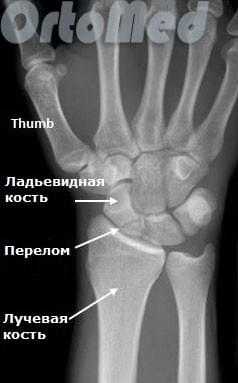

Перелом ладьевидной кости

Причиной травмы становится падение на согнутую кисть, удар сжатой в кулак кистью по твердому предмету или прямой удар по ладони. Как правило, ладьевидная кость ломается на два фрагмента. Возможно внутри- и внесуставное повреждение. К внесуставным переломам относится отрыв бугорка ладьевидной кости. Перелом ладьевидной кости может сочетаться с вывихом полулунной кости (переломовывих де Кервена).

Симптомы перелома ладьевидной кости

Лучезапястный сустав со стороны I пальца отечен, болезненен. Боль усиливается при нагрузке на I и II пальцы. Сжатие кисти в кулак невозможно из-за боли. Для подтверждения перелома ладьевидной кости выполняют рентгенографию в трех проекциях. Иногда линию перелома на снимках разглядеть не удается. В таких случаях, если имеются клинические признаки перелома ладьевидной кости, больному накладывают гипсовую повязку, а через 10 дней делают еще одну серию рентгенограмм. За это время участок кости около линии перелома рассасывается, и повреждение становится более заметным.

Ладьевидная кость является одной из мелких костей запястья. Из всех костей в запястья, переломы ладьевидной кости являются наиболее распространенными. Ладьевидная кость - небольшая кость запястья на стороне большого пальца (с лучевой стороны).

Запястье состоит из восьми мелких костей, известных как кости запястья. Кости запястья образуют два ряда по четыре кости в каждом, которые располагаются между пястными костями и костями предплечья (лучевой и локтевой). Ладьевидную кость можно пропальпировать в области "анатомической табакерки». Эта точка расположена между сухожилиями длинного разгибателя большого пальца и длинной отводящей мышцы.

Первым и обязательным диагностическим моментом является рентгенография поврежденного участка конечности. Чаще всего рентгенография ясно показывает характер перелома ладьевидной кости.

В некоторых случаях, когда по рентгенограмме тяжело определить соотношение отломков назначается компьютерная томография лучезапястного сустава. При таком исследовании можно трехмерно увидеть поврежденную кость, что поможет в определении тактики оперативного лечения перелома.

Если перелом ладьевидной кости происходит без смещения отломков, то линию перелома на рентгенограмме можно и не увидеть. Поэтому очень важно при любой травме кисти выполнить шинирование на 10 дней. На 10 день повторить рентгенограммы кисти и, если перелом все же был, он станет четко просматриваться. Ну а далее выполняют соответствующие лечебные мероприятия (см. раздел лечение переломов ладьевидной кости).